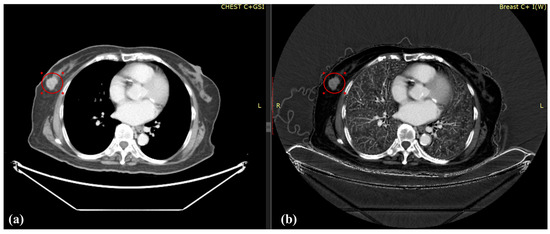

Dual-Energy Computed Tomography for Evaluation of Breast Cancer Follow-Ups: Comparison of Virtual Monoenergetic Images and Iodine-Map

2.2. Image Acquisition

2.3. Image Reconstruction and Analysis